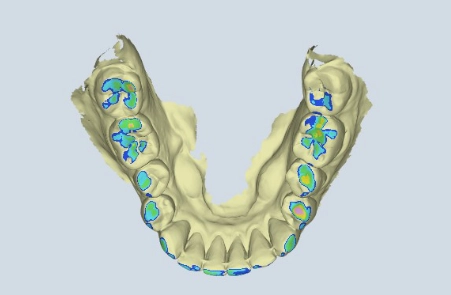

Mit der digitalen 4D-Funktionsdiagnostik erfassen wir Ihren Biss und die Kiefergelenkfunktion in Bewegung, um intelligentere und stabilere Behandlungen zu planen – besonders bei CMD und komplexen Fällen.

Mit unserer digitalen Funktionsanalyse erfassen wir Ihre Kieferfunktion in 4D-Bewegung, um Behandlungen zu entwickeln, die sich genauso gut anfühlen wie sie aussehen. Schnell und strahlungsfrei – für detaillierte Einblicke in Biss, Kiefergelenke und Kaufunktion in Echtzeit und in Zeitlupe.

Sehen Sie genau, wie sich Ihr Unterkiefer in Echtzeit bewegt – und Probleme entdecken, die statische Messungen übersehen.

Bevor eine Behandlung beginnt, nutzen wir das Echtzeit-Kiefertracking, um genau zu sehen, wie Ihr gesamter Kauapparat in Bewegung funktioniert.

Wir beginnen mit einer digitalen 4D-Funktionsdiagnostik, um zu erfassen, wie sich Ihr Kiefer in Echtzeit bewegt. Schnell, berührungslos und strahlungsfrei – für einen vollständigen Blick auf Biss, Gelenke und Funktion. Kein Rätselraten. Nur Klarheit.

Jedes Lächeln erzählt eine Geschichte – und Ihr Kiefer auch. Mit unserer digitalen 4D-Diagnostik sehen Sie, wie Ihr gesamter Kauapparat funktioniert, bevor wir starten – und was wir verbessern sollten.